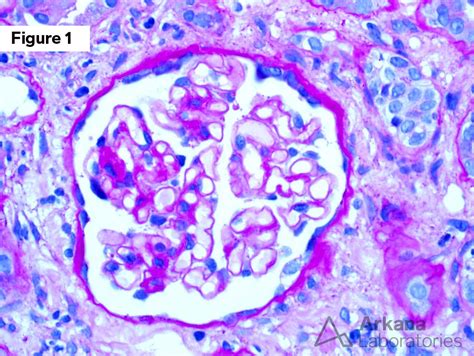

• Light Chain Deposition Disease

The urine free light chain assay measures the levels of free light chains in the urine. This test is particularly useful in patients with renal impairment, as elevated levels of KFLC in the urine can indicate light chain deposition disease or amyloidosis. The results are interpreted in conjunction with serum free light chain levels to provide a comprehensive assessment of the patient's condition.